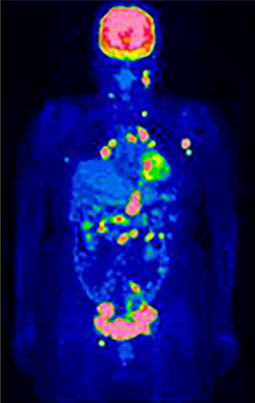

治療後経過観察にて以前の病変近傍に新たな病変出現(再発)

⑤治療中の方の効果判定に役立ちます

がんの治療には手術以外にも、化学療法や放射線療法など、さまざまな方法があります。従来はCTやMRI検査で、治療で効果が出たかどうかを見るのが一般的でしたが、治療後も異常陰影が残っていることがあり、がん細胞は残っているのか治ったあとの瘢痕なのかを判断できませんでした。

FDG-PET検査を用いるとがん細胞の活動性がわかるため、従来の検査より早い時期に、治療効果の判定をすることが可能です。治療効果判定はなるべく早く行うことで、速やかに次の段階の治療方針を検討することができます。

悪性リンパ腫